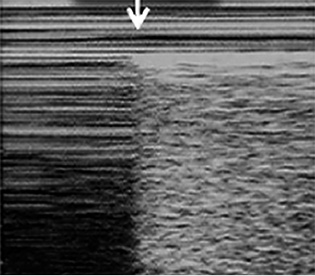

Neumotórax

El neumotórax se produce por la presencia de aire en el espacio pleural, que separa la pleura visceral de la parietal e impide la transmisión normal del movimiento pulmonar a la pared torácica. La ecografía pulmonar es una herramienta altamente sensible para su diagnóstico, especialmente en niños, donde permite una detección precoz, incluso de volúmenes mínimos de aire libre.

• Patrones ecográficos:

– Ausencia de deslizamiento pleural, característico del neumotórax: desaparece el movimiento rítmico entre la pleura visceral y parietal, por la ocupación por aire del espacio pleural.

– Punto pulmón, es un signo específico de neumotórax: punto en que confluyen pulmón colapsado y ventilado (Fig. 11).

Figura 11.Punto pulmón (flecha); a la izquierda se visualiza el patrón de “código de barras”, a la derecha el patrón de “la orilla del mar”.

– En modo M: patrón de “código de barras”, en lugar del patrón normal de “orilla del mar”. Para localizarlo, colocaremos la sonda en el 2º espacio intercostal, línea medioclavicular, recorriendo el espacio de medial a lateral.